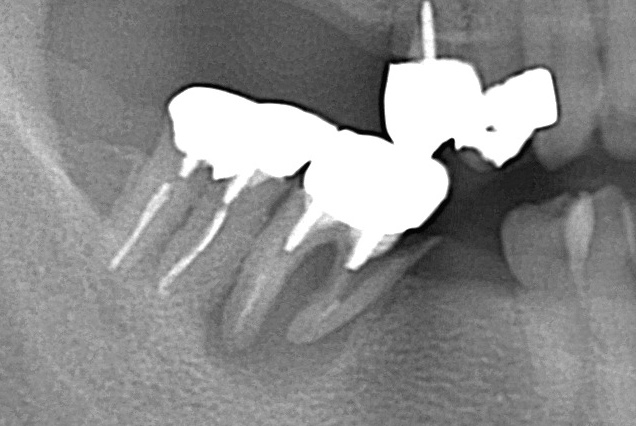

レントゲン写真を撮影することも可能です。

電話診療では、レントゲン写真を撮影できないことはもちろん、歯やお口の状況を見ることができません。

診断に必要な情報を得ることができないので、正確な診断を下すことができません。